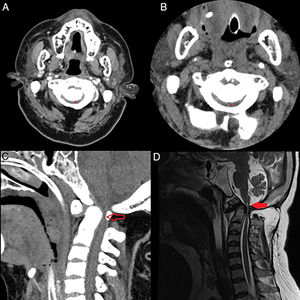

A 34-year-old woman. History: perinatal anoxic encephalopathy; atloaxoid subluxation with critical canal stenosis (Fig. 1A) – neurosurgery being discarded in 2008 due to surgical risk. Seizure episode with head injury (head in cervical hyperflexion). The patient was assisted by out-hospital emergency care (112), initially in asystolia. Resuscitation was started, with recovery of pulse after lung isolation. In hospital: blood pressure 80/50mmHg, heart rate 45bpm, SatO2 100% and temperature 33°C. The full body CT scan revealed no acute lesions and confirmed the already known atloaxoid subluxation (Fig. 1B and C). In the Intensive Care Unit: tetraplegia, areflexia, anal sphincter atonia and absence of respiratory effort in pressure support ventilation. The MRI scan revealed lesions consistent with acute cervical myelopathy (Fig. 1D). With a diagnosis of spinal cord injury without radiographic abnormality (SCIWORA), under noradrenaline perfusion and the administration of dexamethasone, the patient failed to recovery respiratory activity.

(A) Computed tomography scan in 2008: axial acquisition at C1–C2 level showing spinal cord canal stenosis (6mm) (grey asterisk). (B) Computed tomography scan in 2018: axial acquisition at C1 level showing spinal cord canal stenosis (6mm) (grey asterisk). (C) Computed tomography scan: sagittal acquisition showing the already known canal stenosis at the craniocervical junction, with no apparent soft tissue lesions (vacant grey arrow). (D) Magnetic resonance imaging: T1-weighted acquisition showing canal stenosis with diffuse dural thickening and signal alteration in lower bulbar zone, together with cervical intramedullary image consistent with traumatic myelopathy (solid grey arrow).